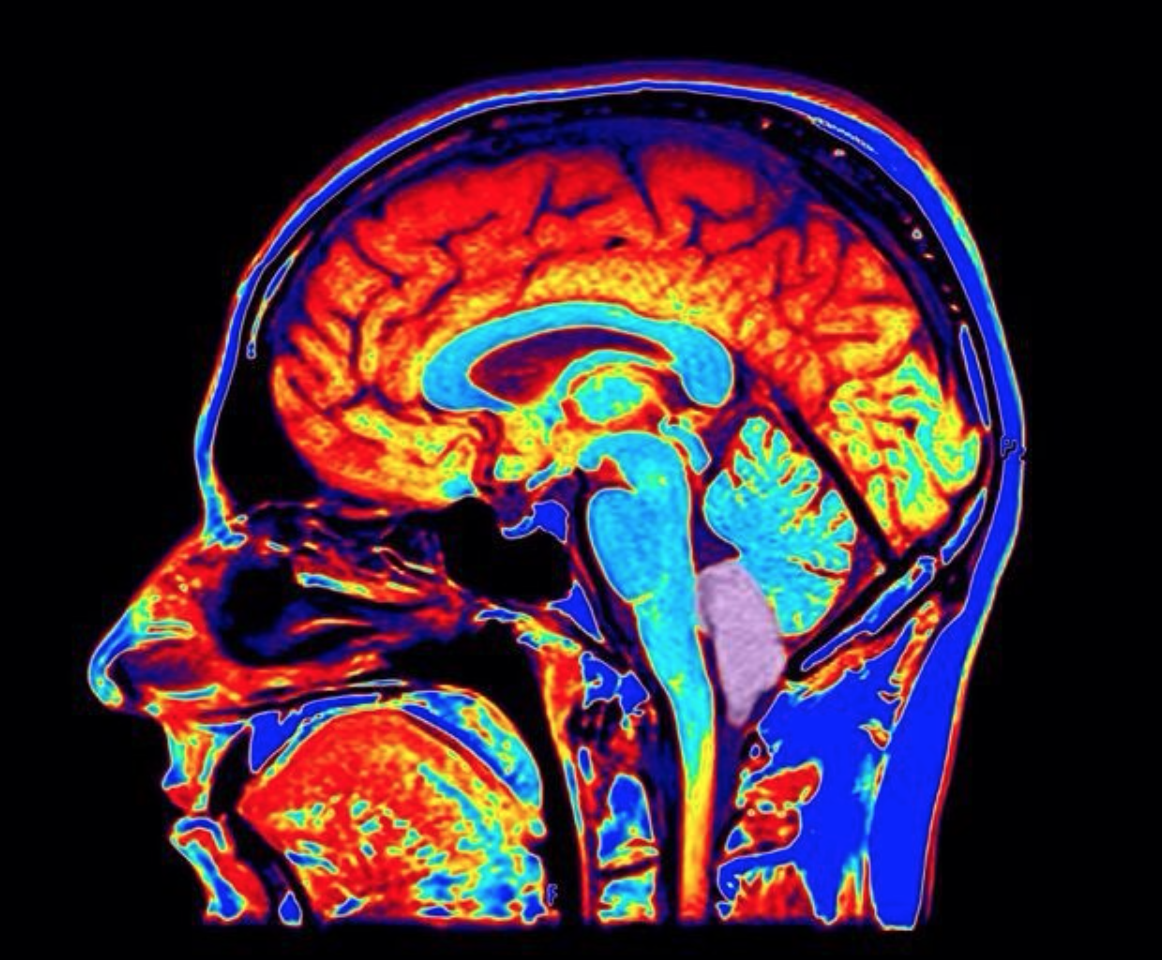

A recent study hooked participants up to brain-scanning machines and placed them into two groups. The first groups was instructed to recall specific negative or stressful scenarios in their lives and then ask themselves the question “what am I feeling right now?”. The machines whirred and recorded all the while. The instructions were similar for the second group, with one little tweak – the participants in group 2 asked themselves, “what is [insert their own name] feeling right now?”.